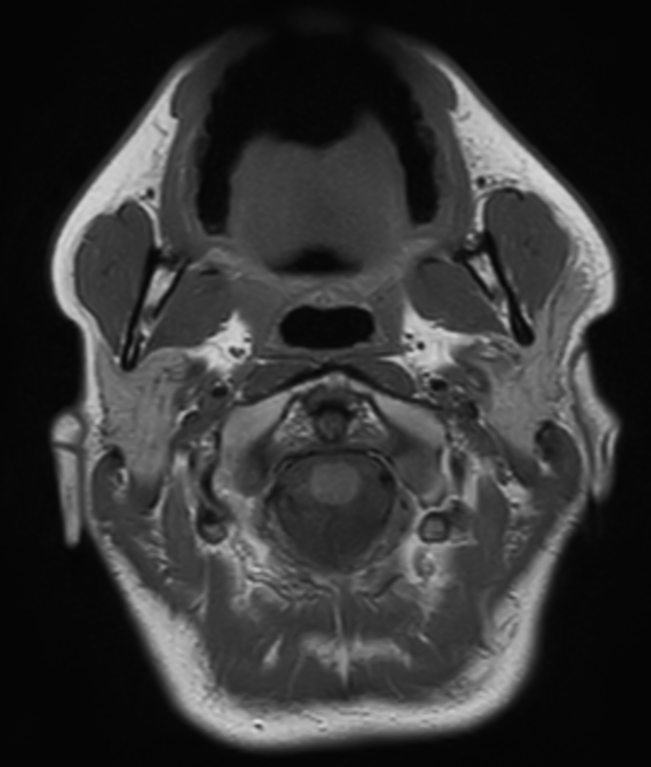

Axial T2w  mDIXON TSE (Water)